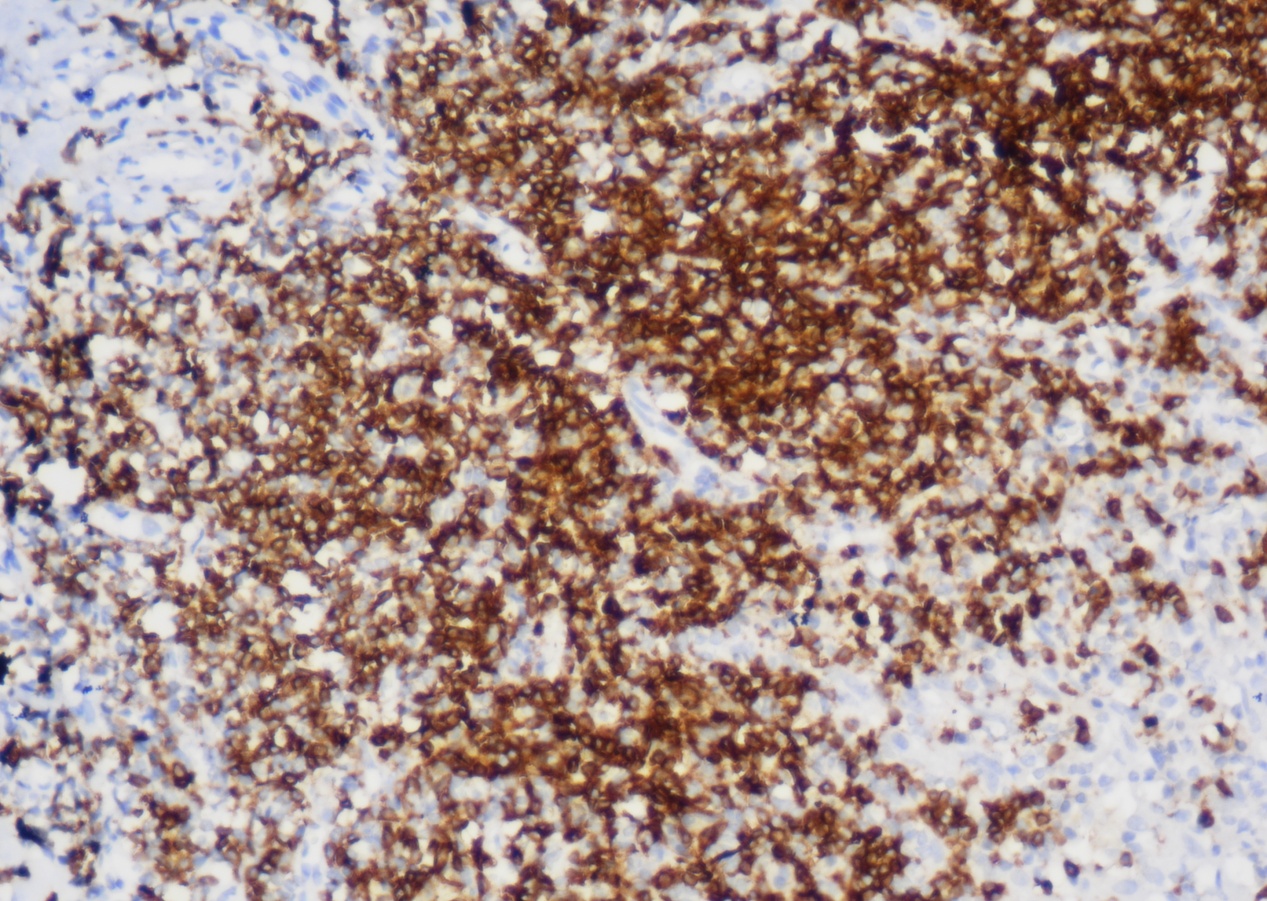

CD2

CD2又称T11/Leu5、LFA-2(Lymphocyte function associated antigen-2,淋巴细胞功能相关抗原-2)、 绵羊红细胞受体,具有调解活化的T细胞和胸腺细胞与抗原呈递细胞和靶细胞粘附的功能。其在所有T细胞和NK细胞中表达,B细胞及正常髓系细胞或肥大细胞中不表达,但表达于肥大细胞增多症的肥大细胞。CD2可用于T细胞淋巴瘤的诊断,对于T细胞标记易丢失的T细胞肿瘤(如ALCL),CD2是较好的补充标记。